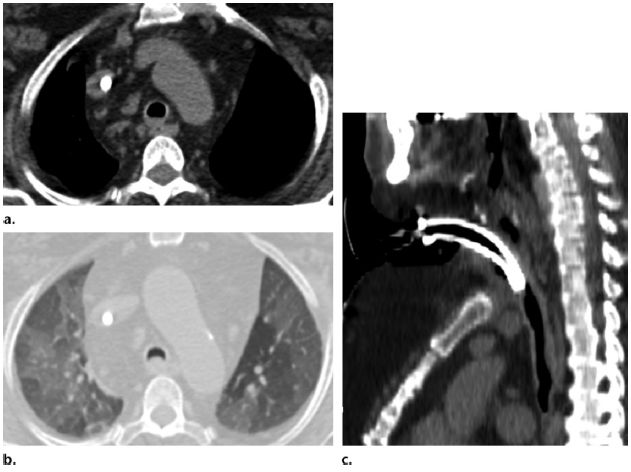

图7 患者,女,64岁,终末期肾病

,气道淀粉样变性需要气管切开。(a)气道ct软组织窗示气道壁增厚,包括气道后方膜部。未见钙化。(b)呼气相可见空气潴留。(c)重建证实长段气管受累

图8 患者,男,75岁,终末期肾病,气道淀粉样变性。(a,b)因呼吸困难进行肺栓塞

治疗,CT图像显示长段气管管壁环形增厚。(c)矢状位重建软组织窗可以更好显示长段气管前壁增厚并可见钙化(箭头)